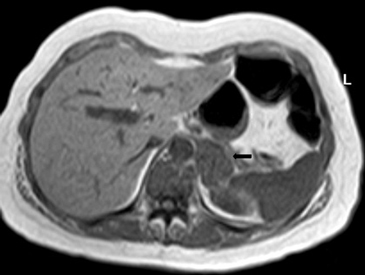

En la TC no contrastada las glándulas suprarrenales normales son homogéneas y simétricas, con una densidad muy similar a la del parénquima renal adyacente (Figura 1 a). Con un medio de contraste ev la glándula suprarrenal se opacifica en forma homogénea, similar al hígado o al bazo (Figura 1 b). Si la cantidad de tejido adiposo retroperitoneal es abundante las glándulas suprarrenales pueden aparecer enteramente rodeadas por grasa y su delimitación es más fácil (Figura 2 a); lo inverso ocurre en pacientes muy delgados con escasa grasa retroperitoneal (Figura 2 b). En RM, en secuencias ponderadas en T1 y T2 convencionales tienen una intensidad de señal homogénea, hipointensa respecto de la grasa adyacente e iso o hipointensa con respecto del parénquima hepático (Figura 3 a y b). En los cortes coronales se aprecia mejor la forma y la posición de las glándulas suprarrenales (Figura 3 c).

Figura 3. Glándula suprarrenal normal en resonancia magnética. (a) Cortes axial ponderado en T1 la señal de la glándula normal (flecha negra) es hipointensa respecto a la grasa retroperitoneal e isointensa respecto al parénquima hepático. (b) Cortes axial ponderado en T2 en que se muestra la glándula suprarrenal derecha (flecha blanca) y (c) corte coronal ponderado en T2 en que se muestra la glándula suprarrenal derecha (flecha blanca) y la glándula suprarrenal izquierda (flecha negra) con similares características de intendidad de señal. 3. Causas y prevalencia de las lesiones suprarrenales